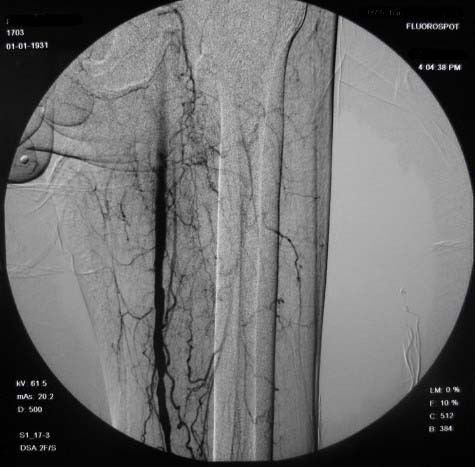

右下肢:

造影方法:取仰卧位,在局麻下,经右股动脉入路,采用改良seldingers技术,置入5f cobra导管于左髂外动脉行dsa,采集速度为2幅/秒,注射速率为6ml/秒,分节段造影;再将导管采用成襻技术放置于右侧髂外动脉,采用左侧同样的方法行dsa,术毕拔管、压迫止血约15分钟,包扎后嘱返病房,术后右足背动脉可扪及搏动。

右侧股浅动脉上、中段多处狭窄,下段闭塞。左侧股浅动脉多处狭窄,国动脉起始部狭窄。可以用球囊扩张配合动脉内溶栓或股浅动脉支架置入。多为糖尿病所致。

双侧股动脉及腘动脉多发狭窄,右股动脉下段闭塞并侧支形成。病变较广泛,球囊可试试,如病人经济不好,最好还是以药物治疗为主。个人意见。